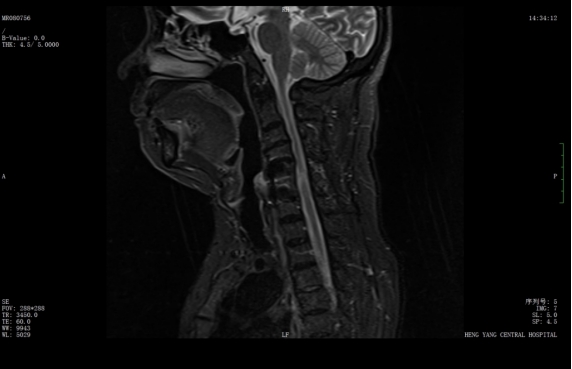

該患者此前因膽囊結石祁東縣人民醫(yī)院治療,來自衡陽市中心醫(yī)院駐該院副院長李攀峰為其主刀進行手術,術后患者恢復良好。后因突發(fā)四肢癱瘓、生活無法自理,為尋求進一步治療,經醫(yī)聯(lián)體通道轉入衡陽市中心醫(yī)院。脊柱外科錢軍博士團隊接診后,迅速組織詳細問診、體格檢查及系統(tǒng)術前評估。查體顯示患者四肢關鍵肌肌力僅I級,感覺功能明顯減退,結合影像學結果,診斷為頸脊髓損傷伴不全癱,有明確手術指征。

術前核磁共振提示:頸椎椎管狹窄、頸脊髓信號改變